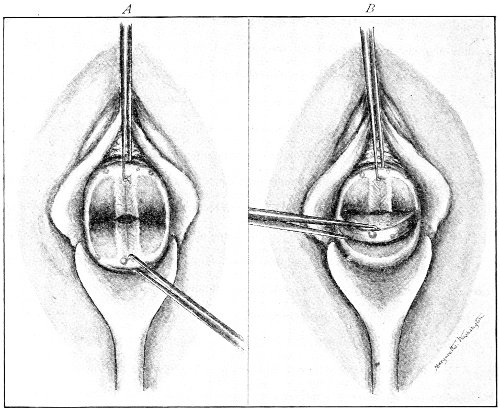

Slight Median laceration of the Perineum.—In this injury the tear takes place through the fourchette. Posteriorly it may extend as far as the sphincter ani muscle. Upward it may extend for an inch up the posterior vaginal wall. The appearance of this tear is shown in Fig. 33. It will be noted that, as this tear takes place in the median line, none of the muscles that support the perineum are involved, nor are the planes of fascia injured. The perineum is slightly split, and the insertions and origins of the muscles and the fascia are slightly separated. The supporting structures of the perineum and the pelvic floor are, however, uninjured.

Fig. 33.—Recent slight median laceration of the perineum: sutures introduced.

If this tear is detected after labor, it should be closed by the immediate operation. A slight tear involving chiefly the cutaneous aspect of the perineum should be closed by three or four sutures introduced from the outside, as in Fig. 33. The needle should be introduced about a quarter of an inch from the edge of the wound. It should not be passed parallel with the plane of the lacerated surface, but should be swept outward and then inward toward the 68 angle at the bottom of the tear (Fig. 34). It may either emerge at the angle and be re-introduced, or it may be passed directly through to the skin-margin on the opposite side of the wound. If the suture is passed in this way, there will be perfect apposition throughout the whole surface of laceration. If the sutures are improperly passed, there may result only apposition of the skin-edges.

Fig. 34.—Diagram representing the correct and the incorrect method of passing the suture for closure of slight perineal laceration.

If the laceration extends up the posterior vaginal wall, two sets of sutures must be introduced—one on the vaginal aspect of the tear, and one on the skin aspect (Fig. 35).